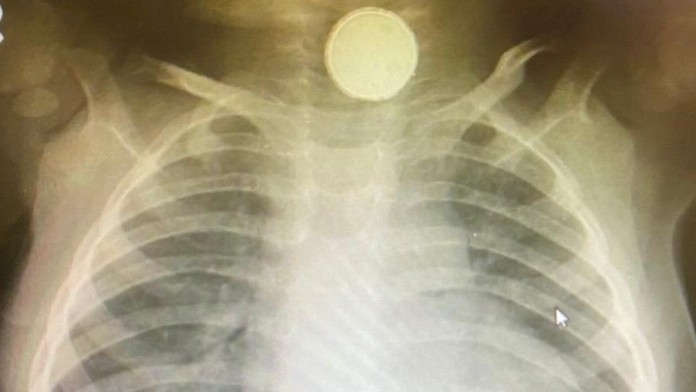

Bábätko mesiace odmietalo stravu, lekári nevedeli prečo. Všetko odhalil až röntgen

Lekári v britskom Swindone dlho nevedeli prísť na to, prečo jedenásťmesačné bábätko dlhodobo odmietalo tuhé jedlo. Píše BBC.

Doktori si mysleli, že Sofia-Grace Hillová mala angínu alebo vírusovú infekciu, ktoré by mohli byť príčinou jej nezáujmu o stravu.

Keď jej však spravili röntgenové vyšetrenie, zostali v šoku. Bábätko malo v pažeráku mincovú batériu.

Momentálne má v hrdle hadicu, ktorá je pomáha ľahšie prijímať potravu. Lekári však nevylučujú, že bude musieť podstúpiť operáciu.

Janet McNallyová, ktorá má tento prípad na starosti, tvrdí, že je veľkým šťastím, že dieťa prežilo. Dodala, že to môže byť preto, že batéria bola stará a nemala už takú účinnosť.